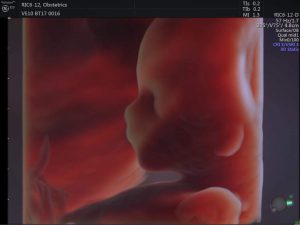

Siêu âm thai là kỹ thuật chẩn đoán y khoa bằng hình ảnh giúp theo ...

Ngày nay, với sự phát triển của công nghệ y học cho phép mẹ nhìn ...

Siêu âm 3D sẽ giúp chúng ta nhận được những hình ảnh tương đối rõ ...